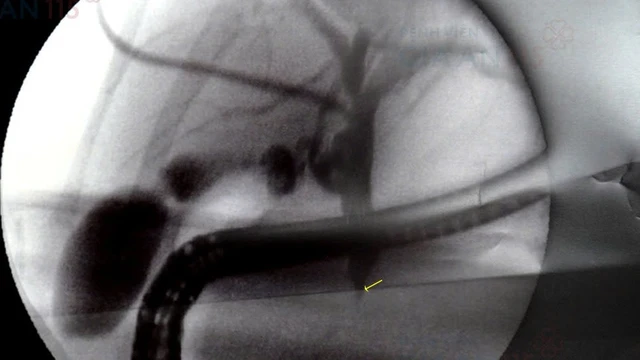

Hiện nay, có nhiều phương pháp để giải quyết tình trạng tắc nghẽn đường mật, trong đó PTBD là một trong những phương pháp được áp dụng phổ biến trong can thiệp y khoa. Vậy PTBD đường mật là gì, được thực hiện như thế nào và khi nào cần áp dụng phương pháp này? Hãy cùng chúng tôi tìm hiểu chi tiết hơn về PTBD đường mật và một số thông tin liên quan nhé!